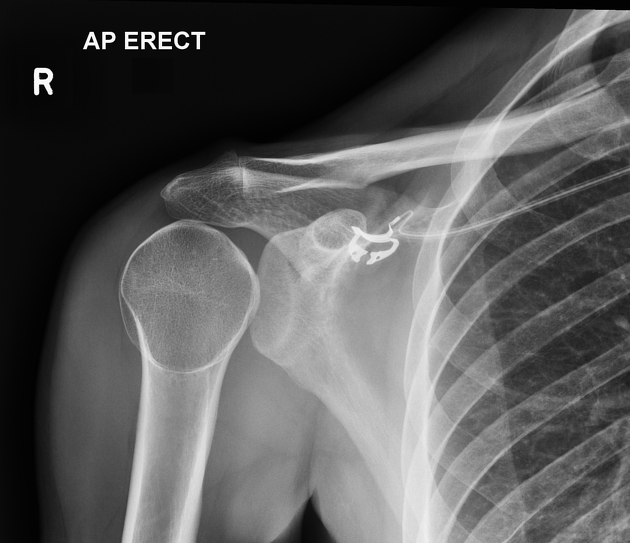

Jordan G. with right shoulder pain?

Posterior shoulder dislocation

(electrocution and "convulsive" seizure MC mechanisms)